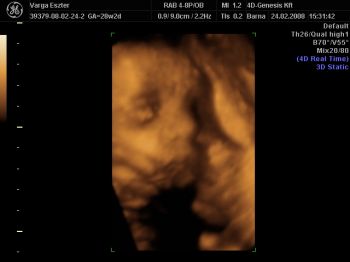

Tegnap voltunk a 4dgenesisben. Természetesen összecsomagolta magát, az arcáról csak pár felvételt tudott készíteni a nő, pedig 1 órán át próbálkozott, hátha kimozdul ebből a pozícióból. Mondta, hogy meglökögeti, nem fog fájni, de a férjem nem engedte. Azt mondta, nem baj, majd amikor megszületik meglátjuk milyen. Azért pár jó fotót sikerült készíteni. Megpróbálom felrakni. Nagyon kedves volt a nő, tényleg mindent megpróbált a lökögetésen kívül. Még csokit is kaptam, meg üdítőt, hátha arra megmozdul. A babával minden rendben, 1400g. A méhlepény 0 fokban érett.

Emma - Nagyon édes a Babó :) Látom, alvó üzemmódban kaptátok el ti is ;) akkor olyan kis nyugodt, kiegyensúlyozott, kisimult a pofijuk a képeken :) Nagyon szép GYerkőc ;)

Igen a kezei. Az egyik könyökét végig az arca előtt tartotta, legtöbbször a térde és a könyöke összeért. Szinte összecsomagolta magát. Volt, hogy a talpát a fejére tette. Ja, és azt mondták,hogy elég sok haja van. Még két képet felrakok. Kép Kép Emma

Köszönöm a dicsérteket! Természetesen, mint minden anyuka, nagyon elfogult vagyok. Állandóan nézegetem, hogy milyen aranyos. Találgatjuk, melyik testvérére hasonlít. Mindenki mást lát benne.

Hihetetlen, hogy milyen pózokat képesek felvenni odabenn. :D A mi picurunk kb. 30 percig le sem vette a lábát a fejecskéjéről. Csak a végén tudtuk elkapni a pofiját egy-két percre. :D